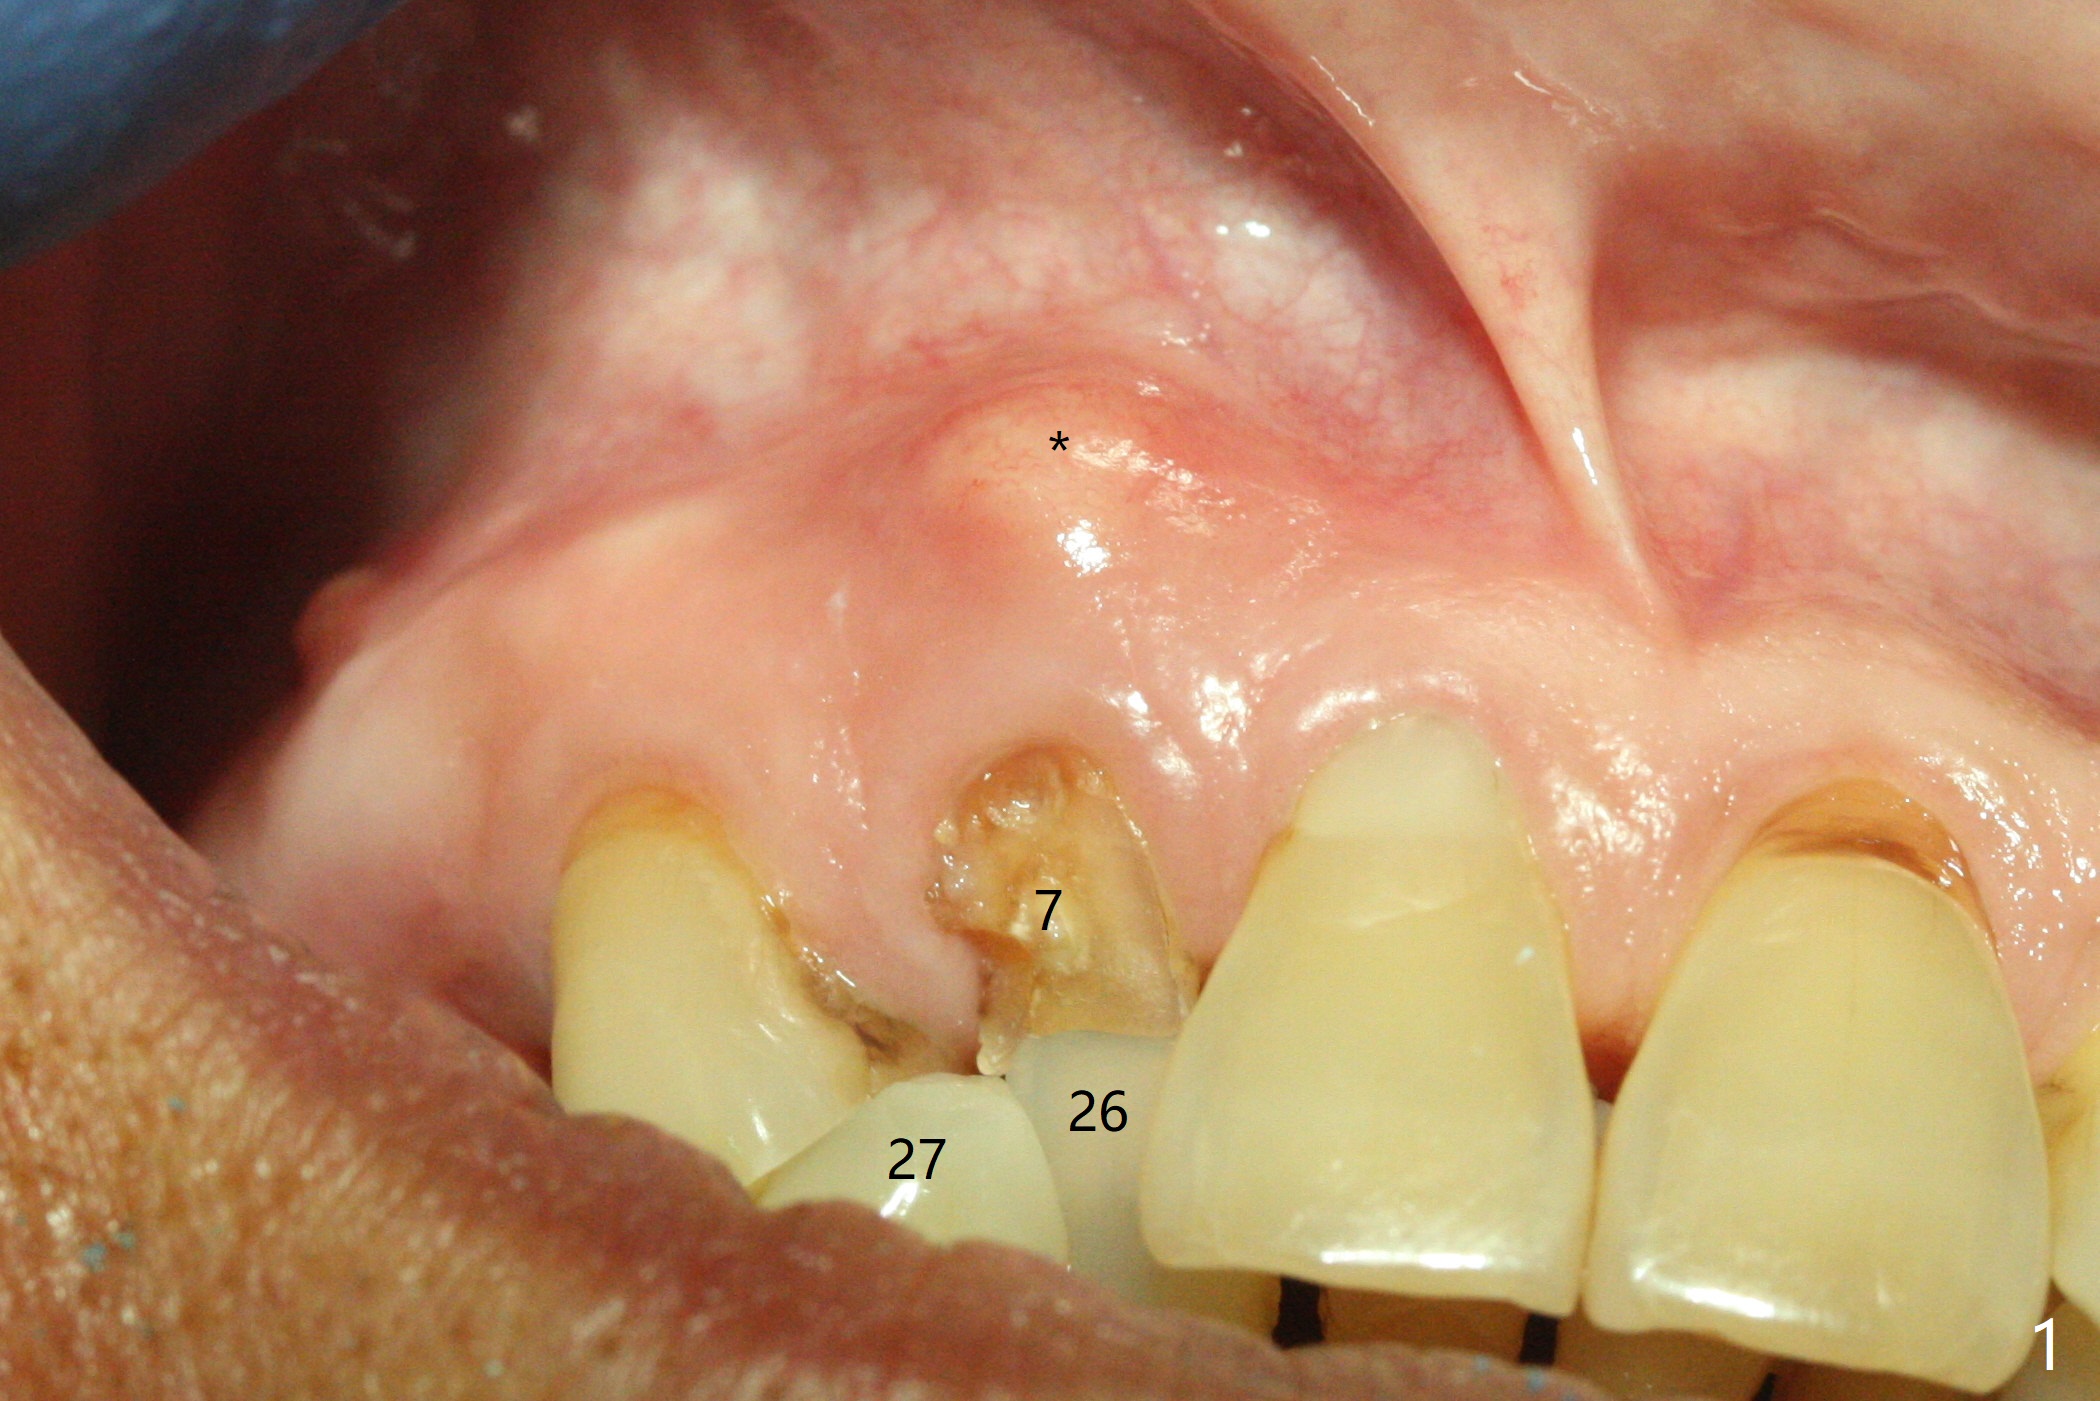

An apical abscess is present when the patient returns for immediate implant at #7 (Fig.1 *); a 2nd challenge is deep bite. After smooth extraction, the apical buccal plate is found to be perforated. Following debridement, a piece of gauze is placed in the apical defect for hemostasis, while osteotomy is initiated palatal (Fig.2). The apical defect seems to be extensive (Fig.3 yellow dashed line). A new trajectory is intended (red arrow) without much success. Before implant placement, bone graft is placed in the apical defect defect area, while a drill (Fig.4 D) is inserted in the finished osteotomy (Fig.5 O). In spite of seemingly large apical defect, the buccal crest bone exists (Fig.4 x). A 3x14(2) mm 1-piece implant is placed with stability; the first round of bone graft is apparently around the apical portion of the implant (Fig.6 *). The coronal end of the implant has to be adjusted several times buccopalatally to accommodate the deep bite. A 2nd round of bone graft following an immediate provisional closes the coronal space of the socket (Fig.7 *). CT will be taken to show the bone graft to repair the buccal plate defect when the patient returns for postop follow-up. In fact the defect is minimal in CT a month ago. The fistula does not disappear 1 week postop, but it is non tender (Fig.8). The patient complains of asymptomatic swelling in the right nostril. CT shows that the large buccal perforation is repaired with large amount of bone graft (Fig.9,10 *). It would be nicer to place the implant slightly more buccal apically (Fig.11 red lines; Fig.12 (preop design)). The buccoapical fistula disappears nearly 1 month postop (Fig.13). The apparently "lifeless" bone graft seems to be harmonious with the surrounding tissue (Fig.14). The periimplant gap reopens with implant mobility nearly 4 months postop (Fig.15), which is related to micro-movement associated with the immediate provisional. The latter is removed. A larger 2-piece implant will be placed in a 2-staged manner if needed (Fig.16). In fact the 3x14 mm straight 1-piece implant (Fig.17) has no mobility when it is retightened, but the trajectory remains buccal. Incision shows that there is no implant thread exposure. A 3x14 mm 15 degree angled 1-piece dummy implant is able to establish the correct trajectory, but there is no occlusal clearance (Fig.18). Micromovement during osteointegration may recreate loosening. Finally using Lindamann bur, the osteotomy is changed so that a 3.5x13 mm 2-piece implant does not need an angled abutment to establish occlusion (Fig.19). There is one palatal thread exposure. Allograft is placed circumferentially, followed by Human Amnion-Chorion Allograft and Collagen Plug. The wound does not heal 8 days postop (Fig.20), as related to the age (79 years old)? The wound appears to heal with a membrane on the surface (Amnion-Chorion one?) 3 weeks postop (Fig.21). The ridge looks wide 3.5 months postop (Fig.22,23). A 4.5x5.5(3) mm appears to be seated incompletely with a gap between the abutment and the implant (Fig.24<). A provisional is fabricated after heavy palatal reduction. Two months later, the provisional fractures. After repositioning the abutment with complete seating and torque (Fig.25), impression is taken. Although the buccal plate is concave, the gingiva remains healthy 10 months post cementation (Fig.26,27).